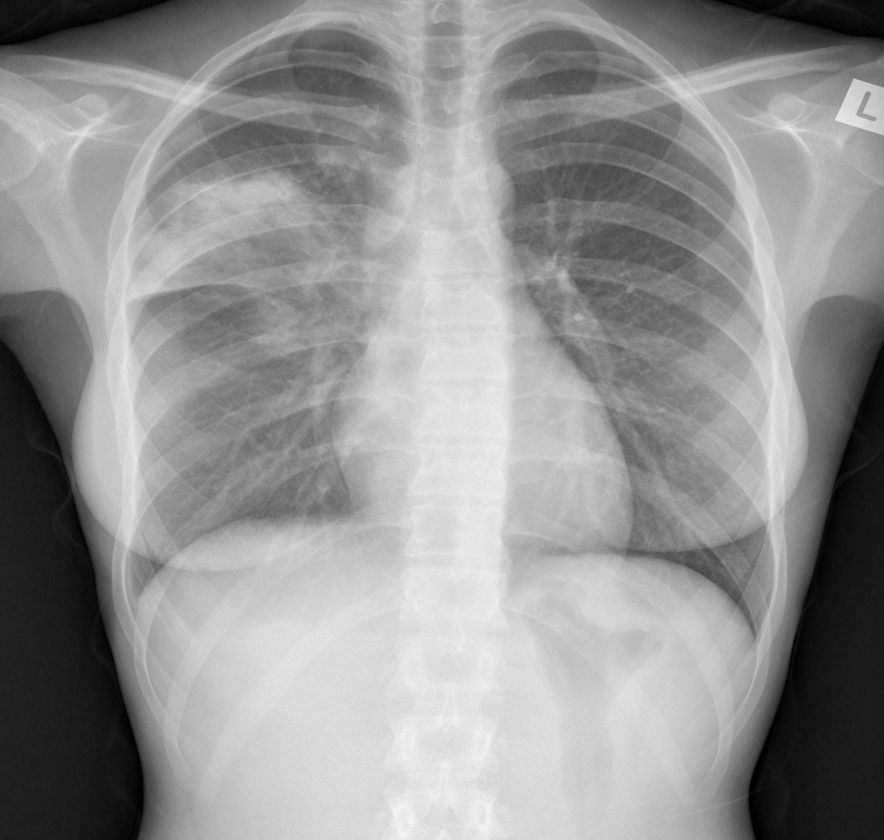

PA CXR

What is this showing? Collapse or consolidation?

Consolidation. Hilar are equal levels. Ill defined appearance